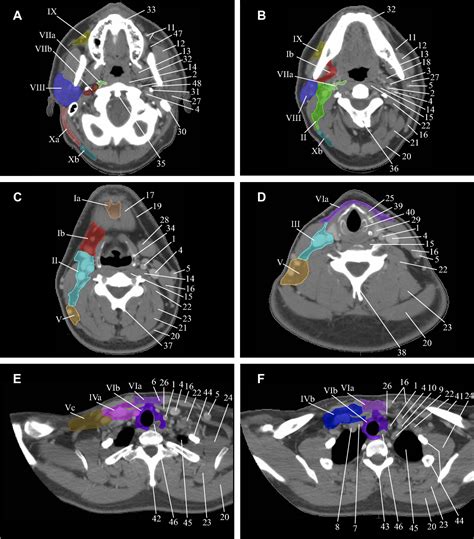

The neck is divided into several levels to facilitate the identification and classification of lymph nodes. This systematic approach is essential for accurate diagnosis and treatment planning. The neck lymph node levels are typically categorized into seven levels, each with specific anatomical boundaries and clinical significance.

Level I lymph nodes are located in the submental and submandibular regions. The submental nodes are found beneath the chin, while the submandibular nodes are situated below the lower jaw. These nodes drain lymph from the floor of the mouth, the tip of the tongue, and the lower lip. They are crucial for detecting infections or malignancies in these areas.

Level II lymph nodes are located along the upper third of the internal jugular vein. These nodes drain lymph from the nasopharynx, oropharynx, and the upper part of the larynx. They are important for evaluating conditions such as tonsillitis, pharyngitis, and cancers of the head and neck.

Level III lymph nodes are situated along the middle third of the internal jugular vein. These nodes receive lymph from the oral cavity, oropharynx, and larynx. They are often involved in the spread of malignancies from these regions and are critical for staging head and neck cancers.

Level IV lymph nodes are found along the lower third of the internal jugular vein. These nodes drain lymph from the larynx, thyroid gland, and lower part of the pharynx. They are significant in the evaluation of thyroid cancers and other malignancies in the lower neck region.

Level V lymph nodes are located in the posterior triangle of the neck, bounded by the sternocleidomastoid muscle, trapezius muscle, and clavicle. These nodes drain lymph from the scalp, posterior neck, and upper back. They are important for detecting infections and malignancies in these areas.

Level VI lymph nodes are situated in the anterior compartment of the neck, between the hyoid bone and the suprasternal notch. These nodes drain lymph from the thyroid gland, larynx, and central compartment of the neck. They are crucial for evaluating thyroid cancers and other malignancies in the anterior neck region.

Level VII lymph nodes are located in the superior mediastinum, below the suprasternal notch. These nodes drain lymph from the thyroid gland, larynx, and trachea. They are important for detecting malignancies that have spread from the neck to the mediastinum.

Evaluation of Neck Lymph Node Levels

The evaluation of neck lymph node levels typically involves a combination of physical examination, imaging studies, and biopsy. Physical examination is the first step in assessing lymph node enlargement. The clinician will palpate the neck to determine the size, consistency, and mobility of the lymph nodes. Imaging studies, such as ultrasound, computed tomography (CT), or magnetic resonance imaging (MRI), can provide detailed information about the size, shape, and location of the lymph nodes. Biopsy may be performed to obtain a tissue sample for histopathological examination.

Imaging studies are particularly useful for evaluating the extent of lymph node involvement and detecting any associated abnormalities. Ultrasound is a non-invasive and cost-effective method for assessing lymph nodes in the neck. It can provide real-time images of the lymph nodes and guide needle biopsy procedures. CT and MRI offer more detailed images and are useful for evaluating deeper structures and detecting metastases.